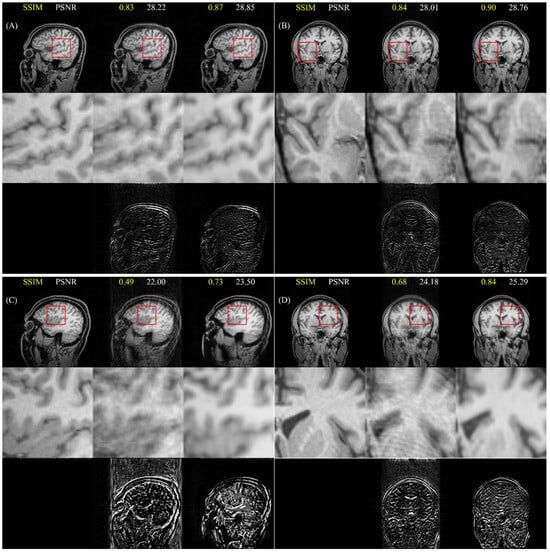

4.4. Cross-Dataset Generalization

5.4. Cross-Dataset Generalization